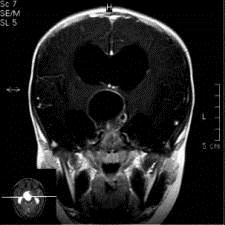

问题 病历摘要:??患者女性,6岁,半年来感觉视力模糊,近10天出现反复头痛,间有恶心呕吐,精神转差,查体:神志清楚,身高90cm,体重25Kg,血压90/55mmHg,右眼视力4.6,左眼视力4.8,双侧视乳头水肿,颈软,伸舌居中,四肢肌张力正常,肌力5级,双侧Babinski征(-)。 该患者就诊时,应作那些必要的检查?